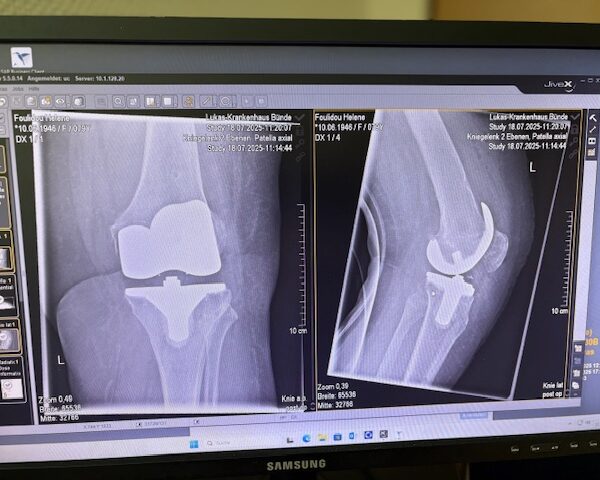

Τα εμφυτεύματα που χρησιμοποιήθηκαν στο γόνατο της ασθενούς είναι της Aesculap: E-Motion Pro, μηριαίο μέγεθος 4, κνημιαίο μέγεθος 4, με ενθέμα (inlay) 10mm.

Η ασθενής κινητοποιήθηκε την ίδια ημέρα μετά την επέμβαση και εξήλθε από το νοσοκομείο την πέμπτη μετεγχειρητική ημέρα.

Ήδη από τις πρώτες εβδομάδες, περπατούσε χωρίς πόνο, με βελτιωμένο εύρος κίνησης.   Η παθητική κίνηση κατα την έξοδο της ασθενούς από την κλινική ήταν E/F : 0-0-120 Επίσης πλήρη σταθερότητα του γόνατος σε κάμψη και έκταση.

Η ακρίβεια του ρομποτικού σχεδιασμού οδήγησε σε άριστη ευθυγράμμιση και φυσική κίνηση, επιτρέποντάς της να επιστρέψει γρήγορα στις καθημερινές της δραστηριότητες και να απολαμβάνει ξανά ποιότητα ζωής και ελευθερία κίνησης!!!